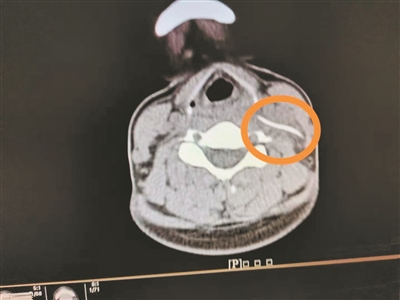

影像檢查顯示頸部異物。

4月1日,陳女士帶女兒到南方醫(yī)科大學(xué)第三附屬醫(yī)院就診,想起自己頸部不舒服,就順便到耳鼻咽喉科就診,副主任醫(yī)師曹慶碩接診后,請患者平躺檢查,此時(shí)陳女士感覺頸部更痛了,醫(yī)生懷疑頸部有異物,于是進(jìn)行了頸部CT平掃,果然發(fā)現(xiàn)左側(cè)頸動脈鞘區(qū)有異物。

明確診斷后,醫(yī)生為陳女士安排4月2日手術(shù),行“頸部側(cè)切開異物取出術(shù)”,術(shù)中見一魚刺橫行于甲狀軟骨平面的咽旁間隙內(nèi),緊貼頸內(nèi)靜脈、頸總動脈后方,周圍炎性組織包裹,幸好頸部血管無損傷,分離包裹的炎性組織,取出異物,長3.3cm。